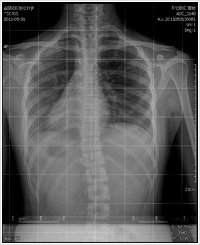

Результат рентгенологического обследования показал, что у меня угол наклона позвоночника был на 15 градусов больше, чем у нормальных людей, изгиб позвоночника которых составляет менее 4 градусов. Это означало, что у меня был сколиоз. После длительных размышлений, я приняла ортотерапию для исправления осанки. Однако тесты, проведенные 31 мая, показали, что лечение мне не помогло.

Я должна была обследовать свой позвоночник еще раз. Мой доктор поразился, сравнив результаты тестирования до молитвы и после: «Ствол вашего позвоночника был искривлен на 15 градусов, а теперь он практически нормальный». Я благодарна Богу Отцу, Который исцелил меня. Аллилуйя!

1. До молитвы (31 мая 2011г.) 2. После молитвы (24 июня 2011г.)